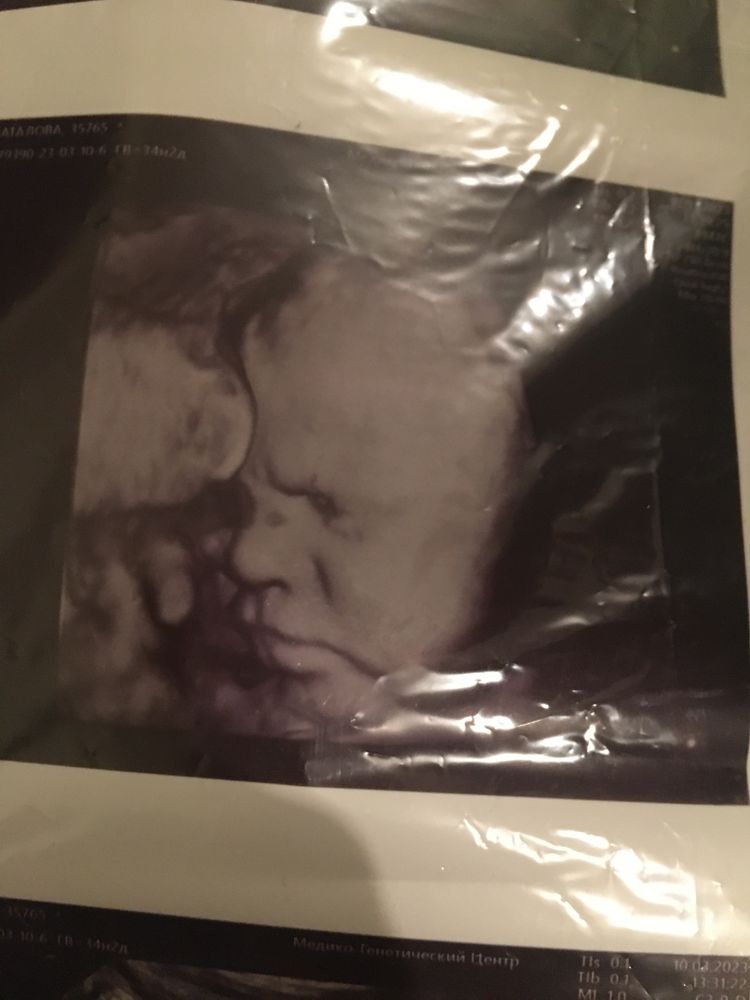

Вопрос, скорее, риторический. Понятно, что форум есть форум и у каждого свое мнение и своя история. У меня ситуация странная: на скринингах было всё хорошо, только на первом ТВП=2,9, но по крови риски пришли низкие, и генетики меня не приняли, хотя я звонила и пыталась записаться. На втором скрининге вообще без замечаний. Появились проблемы только после третьего: ризомелическое укорочение трубчатых костей, гепатомегалия, двусторонный крипторхизм, многоводие. Делала несколько экспертных узи, ездила на консультацию к генетику. Он рекомендовал кордо. Пояснил, что риск хромосомной аномалии есть. Понятно, конечно, что прервать беременность по результату инвазивной диагностики уже нельзя, но хотелось бы знать, к чему готовиться. Что думаете?